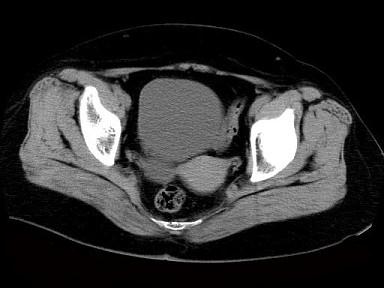

问题 女性,27岁,体检时B超发现右侧附件区囊性占位性病变,行CT检查,下列说法错误的是 ( )

选项 A、此为卵巢浆液性囊腺瘤 B、此为卵巢囊肿 C、病灶边界清晰 D、病灶为单房,壁薄,无分隔 E、病灶来源于右侧卵巢

答案 A